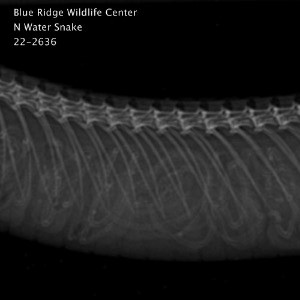

This Northern Watersnake was brought into care after catching a hook in the upper jaw. During the patient’s full exam, it was also noticed that the tail tip was broken, necrotic, and in need of amputation. Other than these small injuries, this snake was bright, alert, and feisty.

Radiographs taken to assess tail damage also revealed that this snake will soon be a mom! Northern water snakes are viviparous, meaning that they give birth to live young rather than laying eggs. This species gives birth this time of year and can have litters of up to 50! We are hopeful that we will be able to release this snake before she gives birth so that her babies can be born in the wild.